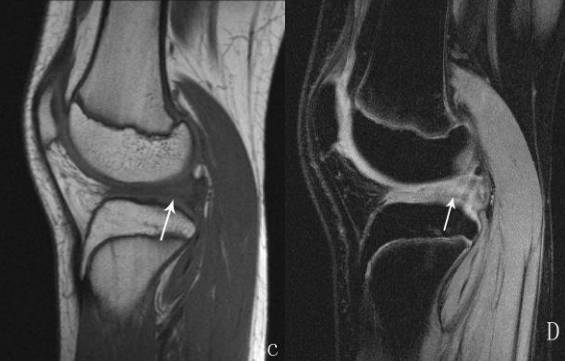

1、股内侧肌。2、股四头肌肌腱。3、髌骨。4、髌韧带。5、前交叉韧带。6、胫骨。7、腓肠肌内侧头。8、后交叉韧带。